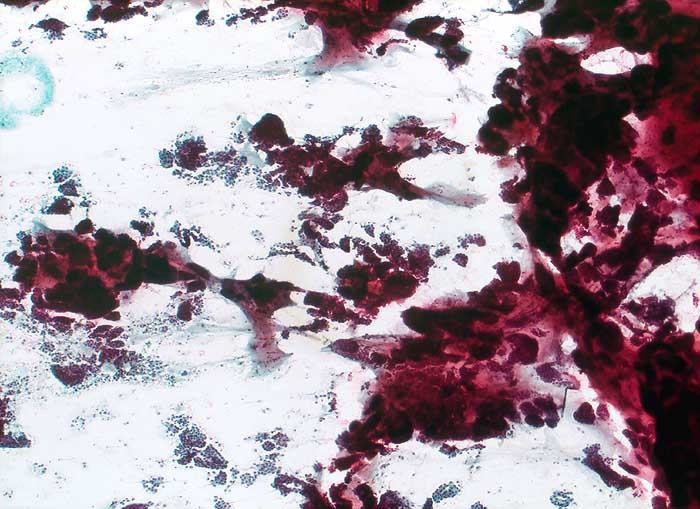

Homogene oder schlierenförmige extrazelluläre Schleimmassen mit Inseln von Tumorzellen mit geringen Kernatypien sind pathognomonisch für das muzinöse Mammakarzinom. Die Zellzahl ist meist nicht sehr hoch. Die Zellen liegen einzeln oder in kleinen kugeligen oder pseudopapillären Verbänden. Der Schleim erscheint in der Pap Färbung blau-grau bis rötlich. Siegelringkarzinome zeigen grössere intrazytoplasmatische Schleimvakuolen.

Unten werden zwei Beispiele von typischen muzinösen Karzinomen gezeigt.